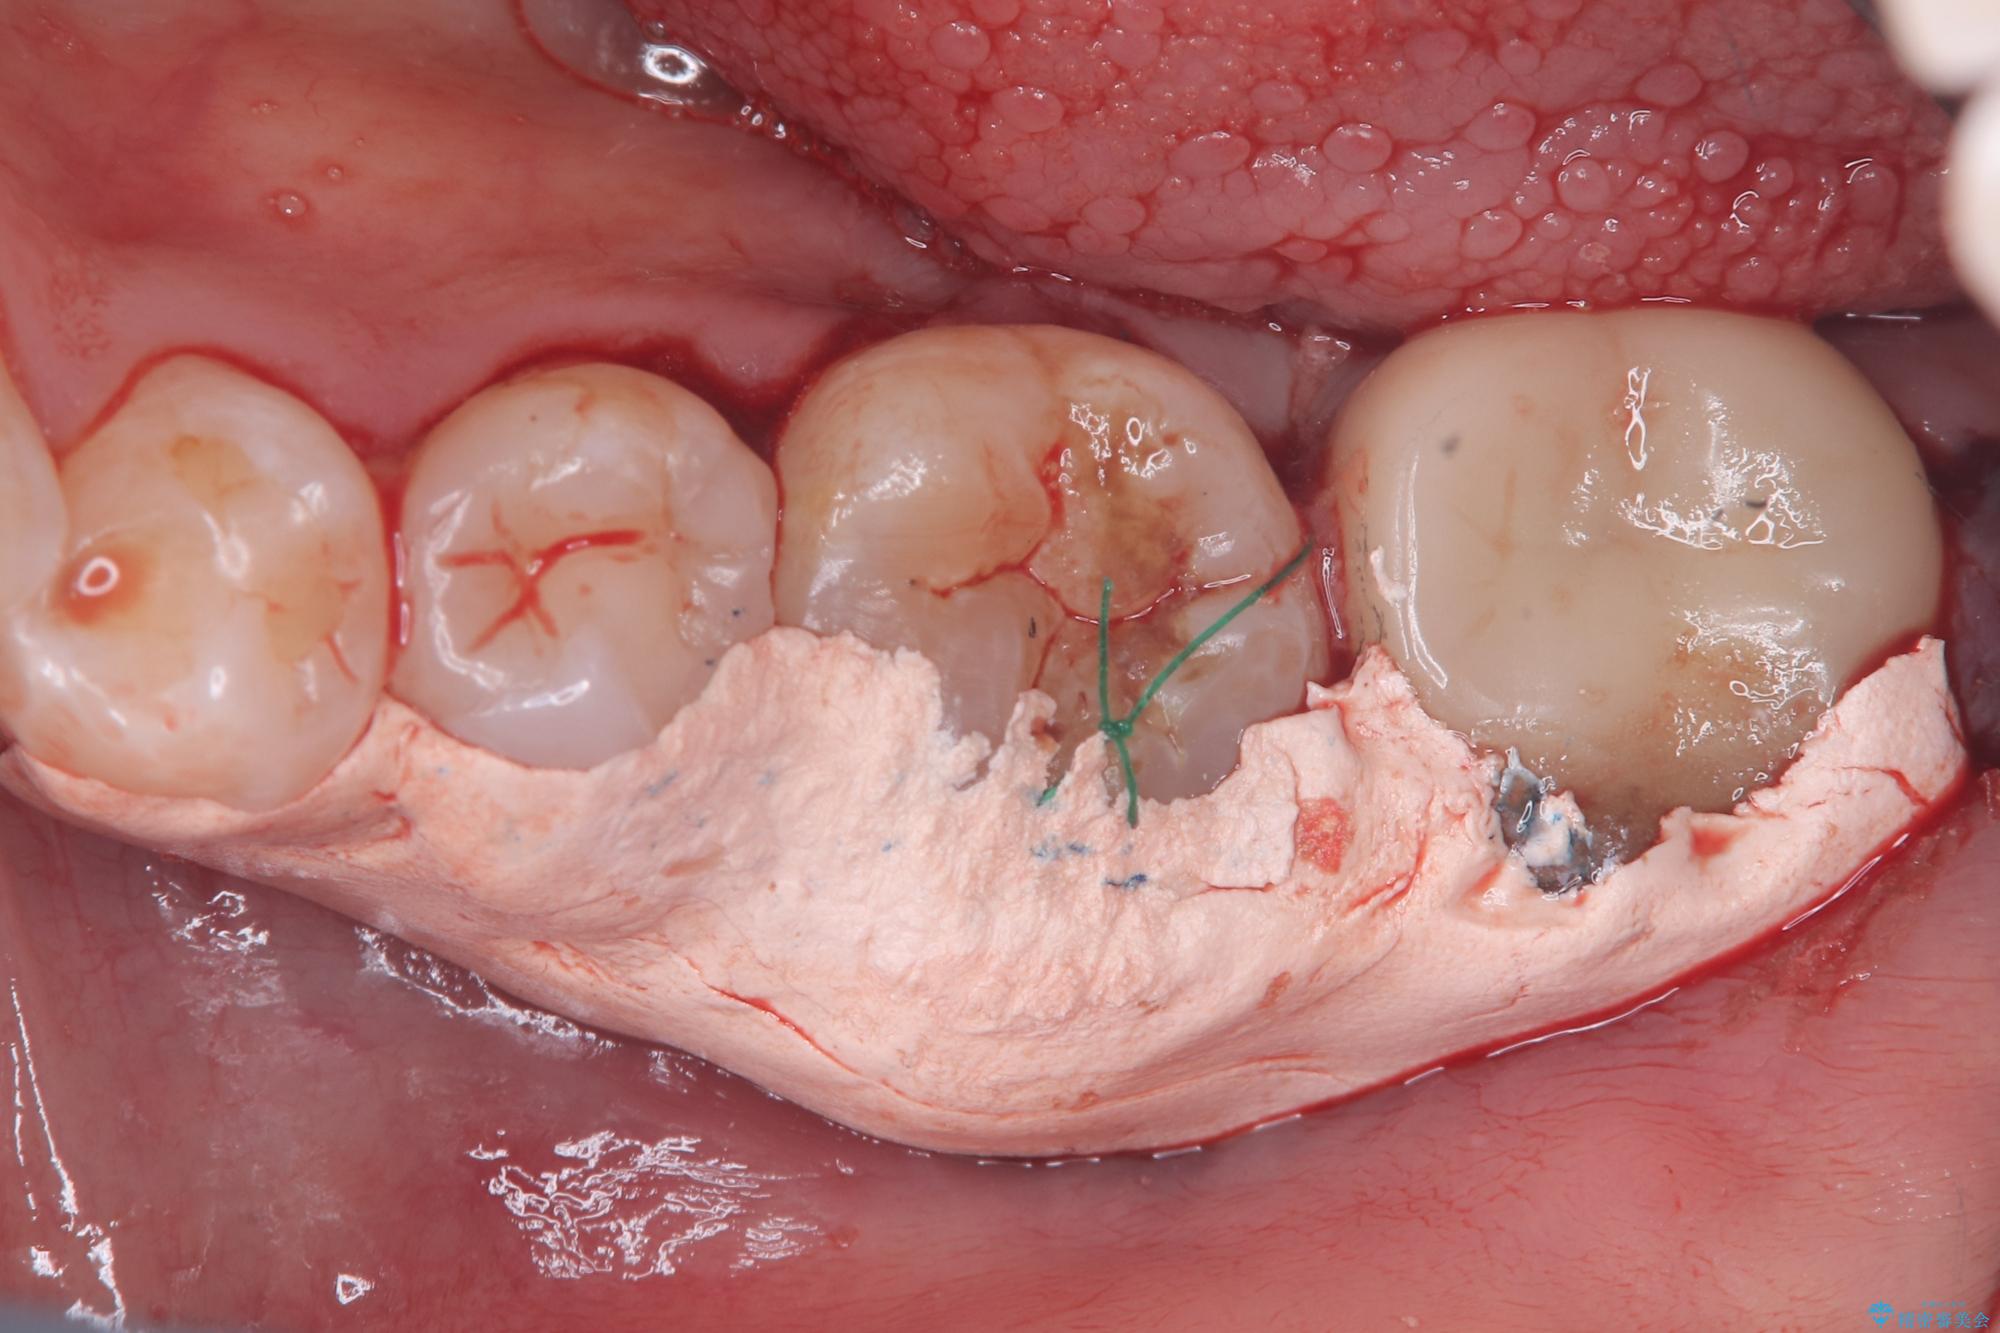

保存が難しい左下6番目の歯を抜歯し、左下8番目の歯(親知らず)を抜歯窩に移植しました。歯牙移植後の動揺防止のため暫間固定を行っています。

また移植後2週間経過時点で根管処置が必要となります。

骨との定着を確認し、今後矯正治療を行う予定のためレジン冠をセットしています。